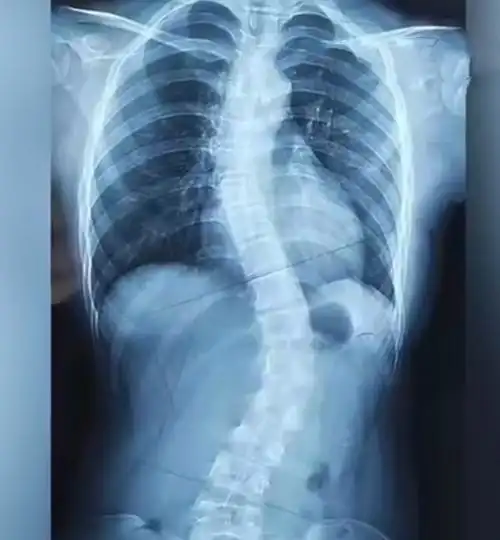

新苗脊柱侧弯医体治疗体系4060度治疗好转的病例

先天性脊柱侧凸站立位全脊柱正侧位:胸椎右侧弯,cobb角53°(t2-t7),t3